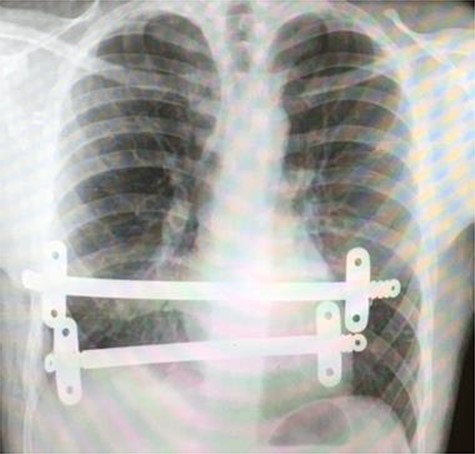

Chest X-ray taken after the removal of the upper substernal bar. The second bar is seen, traversing the diaphragm, having migrated into the stomach.

Our patient was followed up annually. After two and half years, he developed a right-sided wound infection, initially treated with antibiotics. It was decided to remove the bar for prevention of recurrent infection. The chest X-ray showed migration of the lower-placed bar (Fig. 2). The upper bar and associated stabilizers were removed through the bilateral small incisions without any complication; however, the lower bar was not palpable. Therefore, a left-side thoracotomy was performed; however, the bar was not found in the chest. The incision was extended to a midline laparotomy (Fig. 3). This revealed an erosion of the bar in to the stomach after passing over the left lobe of the liver (Fig. 4). The bar and stabilizers were completely removed, and the hole in the stomach was closed directly with sutures. The patient was discharged home without any further complication after successful recovery.